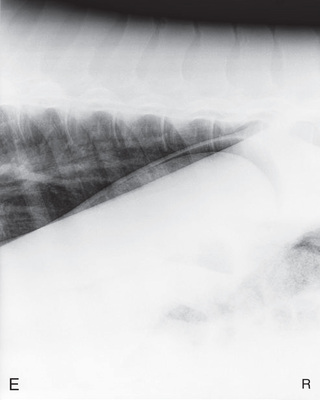

| Thorax | Lateral (Fig. 24.60) | Affected side | Horizontal beam on opposite side. | See comments later for specifics: | Patient standing. Portable unit not powerful enough. |

| Abdomen | Lateral (Fig. 24.61) | On side (most lesions on midline). | Opposite side. | Last rib for small horses: | Multiple laterals required for larger patients. |